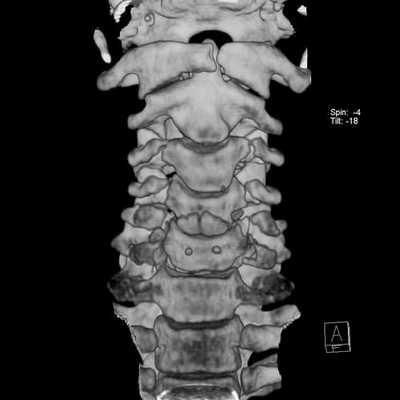

4. КТ костного трансплантата позвоночника:

• Бесконтрастная КТ:

о МСКТ позволяет оценить положение трансплантата, целостность замыкательных пластинок, диагностировать перелом трансплантата, тел позвонков

(Слева) Сагиттальный КТ-срез: типичная картина несращения костного трансплантата: вокруг костного трансплантата, использованного для замещения резецированного тела L4, сформировалась зона просветления. Задний фрагмент тела L4 смещен назад, тело L3 коллабировано и склерозировано.